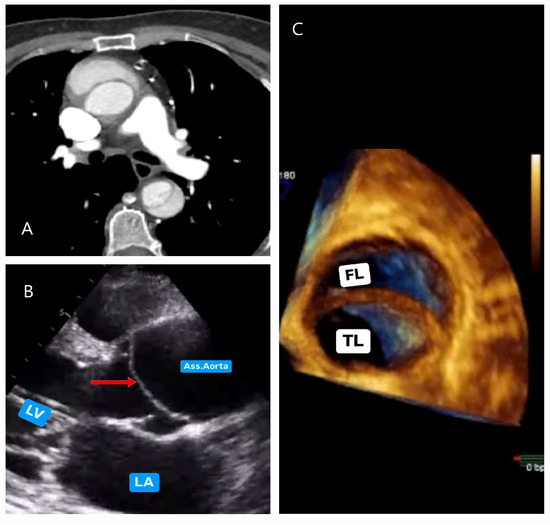

5.2.2. Echocardiography

5.2.3. Computed Tomography